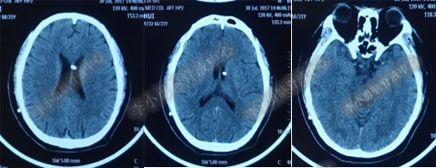

2017年6月19日(第1次内镜术后404天即一年零39天),因原症状加重,第2次住入该院。2017年6月20日(住院第2天),复查头部MRI(图-5)。

图-5:2017年6月20日头部MRI

2017年6月27日(分流术后5天),复查头部CT(图-6)显示幕上脑室及第四脑室均有所缩小。

图-6:2017年6月27日头部CT

图-7:2017年7月30日头部CT

图-8:2017年9月18日头部CT

图-9:2017年10月15日头部CT